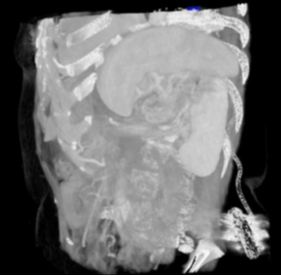

Figure 1: Coronal image of spleen during CT abdominal scan with contrast.

The CT scan demonstrated abnormal rotation of the spleen on its axis, with the hilum facing laterally (yellow arrow) and engorged splenic hilar vessels. There was a 360-degree rotation of the splenic artery and vein, accompanied by heterogeneous enhancement of the spleen. The overall splenic rotation towards the midline corroborated potential torsion.